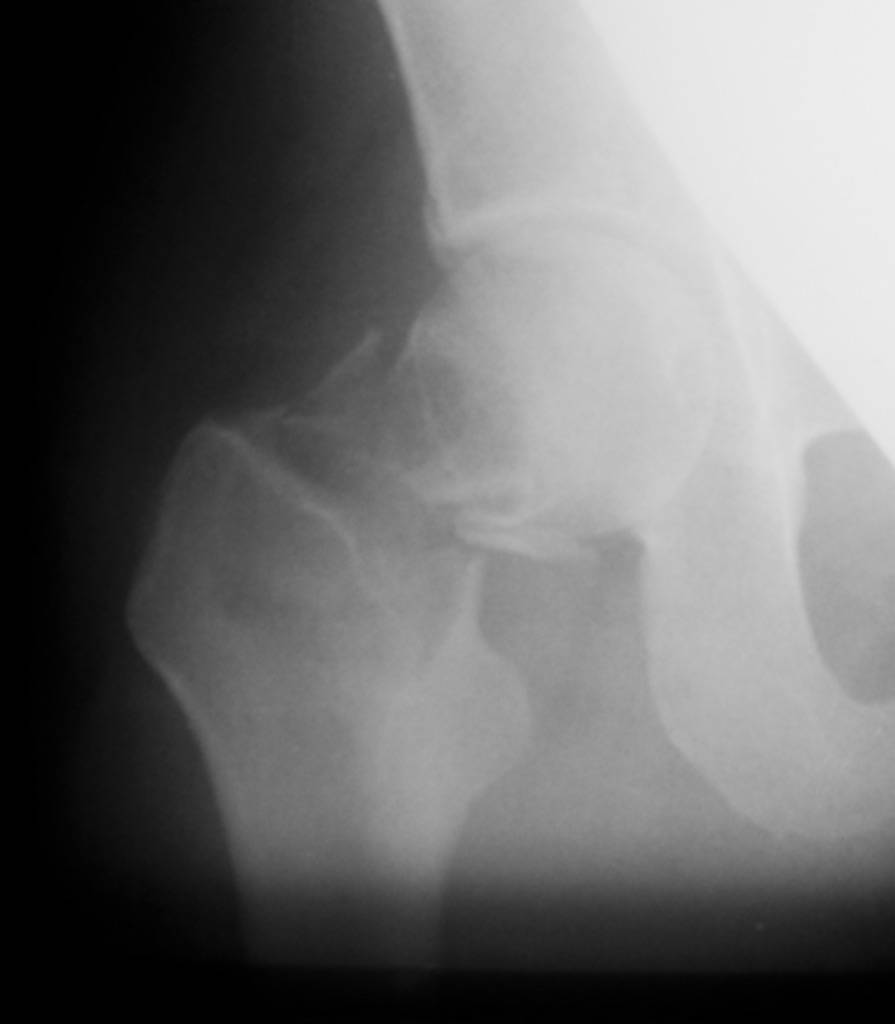

Приношу извинения, думал, что на прилагающейся рентгенограмме видно, что перелом произошел на месте обширной кисты, занимающей шейку и вертельную область. По характеру перелом многооскольчатый, дуга Адамса также представлена в виде осколков.

"Поправил" рентгенограмму. Так не лучше?